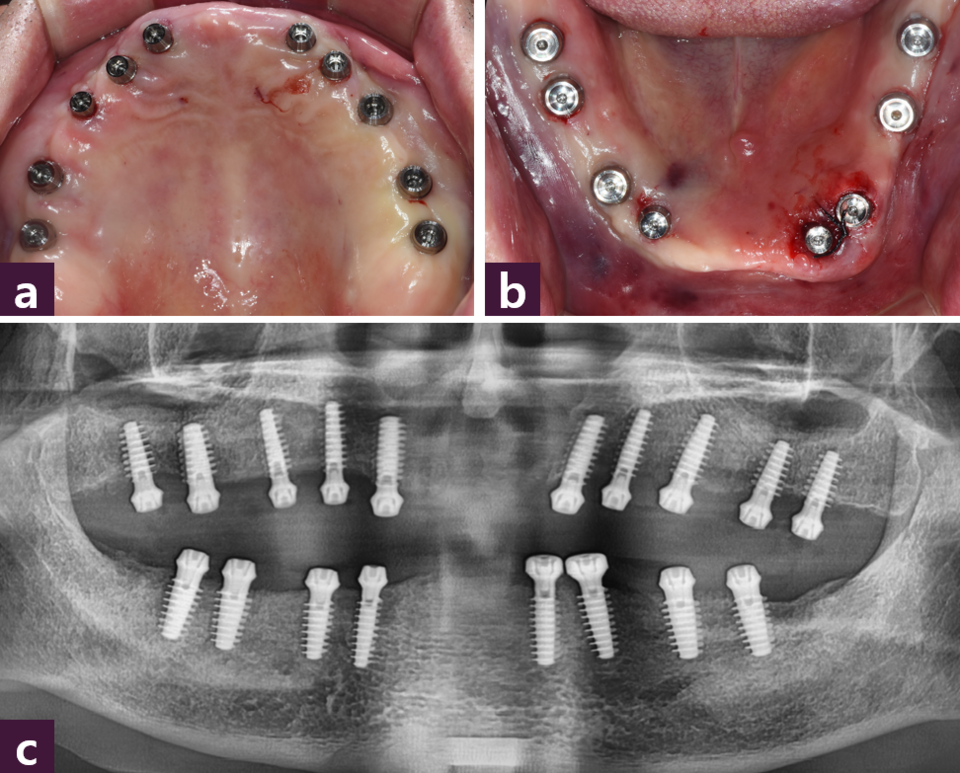

본 증례에서는 치아의 평균 근원 심 폭경을 참고하여 캘리퍼로 근원심 간격을 표시한 후 Magic Guide Pin을 꼽고 [그림 2]

CBCT를 촬영하여 식립 예정부위의 치조골 상태와 식립 방향을 분석하여 flapless 시술법으로 상악에 10개, 하악에는 좌측 견치의 발치 즉시 식립을 포함하여 8개의 MagiCore를 2일에 걸쳐 식립하였다 [그림 3~4].

식립 직후 고정성 PMMA임시치아를 제작하기 위해 transfer type impression coping 을 연결하고 폴리비닐 실록산 인상재를 이용해 상하 인상을 채득한 뒤 [그림 5],

작업 모형을 제작한 후 상하 작업 모형을 반조절성 교합기에 마운팅하여 맞춤형 지 대주(titanium customized abutment)와 상하악 모두 전치부와 양측 구치부로 3분획한 PMMA 임시치아를 제작하였다 [그림 7].